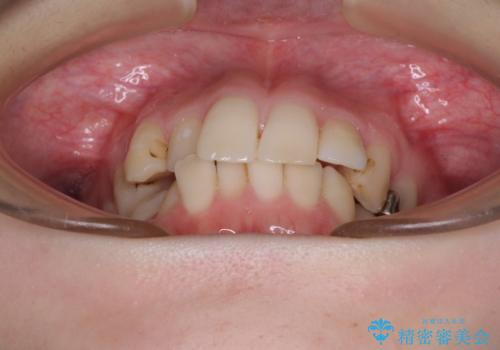

- 前歯のデコボコをクロスバイトを気にして来院された患者様です。

上顎骨の横幅が狭く、上下ともに内側に倒れ込んだ混み合った歯列となっていました。

急速拡大装置により上顎骨を側方に拡大し、ワイヤー装置により歯列を整えることとしました。

矯正治療後には、目立つ銀歯と隣接するむし歯をセラミックインレーにて修復治療することとしました。